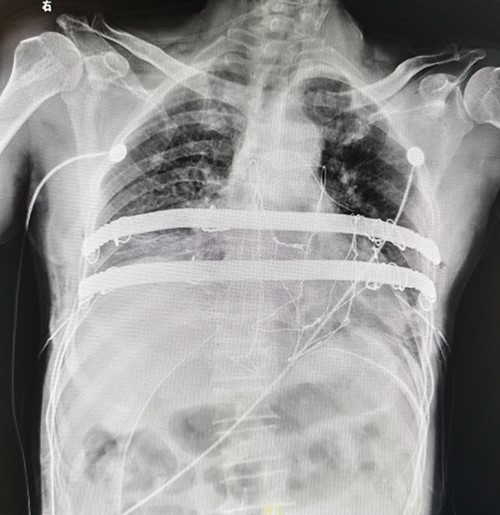

The patient is a 65-year-old male. He was found to have a mass in the middle of the chest wall 1 year ago, without any discomfort. In the past 2 months, the mass grew rapidly with local pain. The patient was recently admitted to our hospital for surgery. Preoperative physical examination showed that there was a mass in the middle of the anterior chest wall, about 5 × 5 cm in size, with obvious tenderness and unclear boundary (Fig. 1). Imaging examination revealed a sternal tumor, which was located in the sternal body and invaded the surrounding costal cartilages (Fig. 2). The operation was performed under general anesthesia. In supine position, a longitudinal incision was made in the middle of the anterior chest wall to expose the tumor, and the tumor was removed along the periphery. The resection location was ~3 cm away from the border of tumor. After resection, a huge defect was formed in the middle of the anterior chest wall. Incisions were made on the lateral chest wall to expose the surrounding ribs. Wenlin procedure was performed with two steel bars [6, 7]. The curvature of the bar was the normal curvature of the chest wall. Both ends of the bar were firmly fixed with two adjacent ribs [8]. A mesh was woven between the two steel bars and the upper and lower ribs with steel wires, and the inner and outer sides of the steel bars were padded and fixed with fiber membranes. Drainage tubes were placed in both thoracic cavities and surgical fields (Fig. 3). After the incisions were closed, the operation was completed (Fig. 4). The operation time was 95 min, the intraoperative bleeding was 30 ml, and no complications occurred during the operation. The patient recovered smoothly after operation. Postoperative X-ray examination showed that the positions of the steel bars were normal (Fig. 5). He was discharged 10 days after operation.

(A) Exposing tumor; (B) Resection of tumor; (C) Complete Wenlin procedure with two steel bars; (D) Wires mesh; (E), Fiber membrane is placed inside the steel bars and (F) The fiber membrane is placed outside the steel bars.